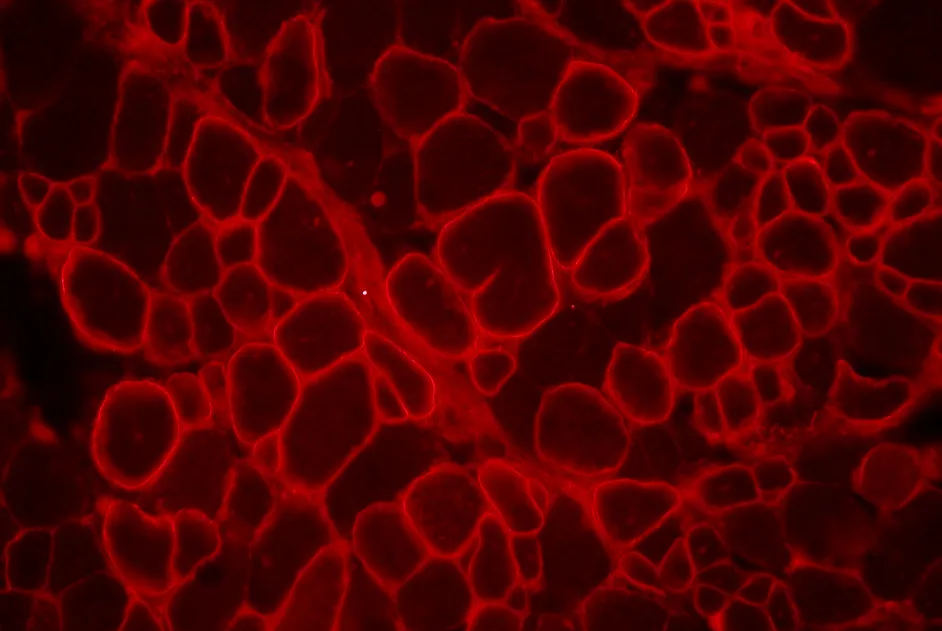

Une collaboration anglophone a identifié un nouveau gène à l’origine de maladie de Charcot-Marie-Tooth de type 2 (CMT2) : le gène MARS.